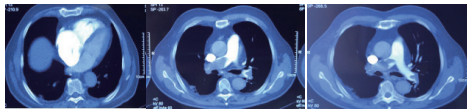

1 经典的挽救性溶栓治疗策略可能带给医生更多的是被动和难度例1 男性,28岁,体质量90 kg。主诉“胸闷、憋气1周加重1 d”。既往:体健;喜久坐(平均10~15 h/d);否认手术史、外伤史;入院查体:神志清楚,体温36.8℃,血压128/80 mmHg(1 mmHg=0.133 kPa),脉搏120次/min,呼吸26次/min,脉氧饱和度96%(安静,空气氧),未见明显乏氧征。双肺呼吸音清,未闻及干湿性啰音。心率120次/min,心律齐,P2 > A2,心界无扩大,无杂音。腹软,无压痛,肠鸣音正常,双下肢无浮肿。神经系统查体未见异常。血气分析(空气氧)提示pH 7.514,PaCO2 27.2 mmHg,PaO2 67.1 mmHg,SaO2 95.0%;D-Dimer:3 035 ng/mL,FDP 33.08 μg/mL,FBG 4.520 g/L;PLT 179.0 G/L,TNI 0.08 ng/mL,BNP 882.00 pg/mL;ALT 38 U/L,AST 17 U/L,CREA 82.6 μmol/L,血Na+、K+、Cl-正常范围;超声心动图(Ultrasonic Cardiogram,UCG)提示:右心增大,肺动脉主干及右肺动脉增宽,肺动脉主干32 mm,三尖瓣反流(重度),反流面积8.6 cm2,TI法估计SPAP为67 mmHg、左室舒末内径50 mm、左室E/A:45/38 cm/s, 左室壁厚度及运动正常,未见节段性室壁运动障碍;双下肢静脉超声提示左侧股静脉血栓形成可能(完全型)。心电图(图 1所示)提示窦性心动过速;肺动脉增强CT(Computed tomographic pulmonary angiography, CTPA)提示双肺主干明确充盈缺损(图 2所示)。入院诊断:急性肺血栓栓塞症(中高危)。入院后给予抗凝治疗(依诺肝素钠90 mg,皮下注射,1次/12 h)重叠华法令治疗的第4天D-Dimer升至47 482 ng/mL,第6天2 411 ng/mL。第7天常规复查双下肢超声未见新增血栓形成,复查UCG(当天INR 2.25)提示右心房漂浮血栓,并随心脏蠕动明显(图 3所示)。在准备胸外科手术取栓的过程中出现血压下降至70/40 mmHg,脉氧饱和度降至45%,立即给予气管插管并系统溶栓治疗(r-tPA 100 mg于2 h输注),溶栓治疗1.5 h患者血压逐渐回升并趋于稳定、溶栓治疗3 h自主呼吸开始恢复,于插管3天后(住院第10天)拔出气管插管,成功撤离呼吸机。溶栓过程中曾经出现消化道、气道出血,血红蛋白下降1.9 g/dL,未予输血治疗。溶栓后复查CTPA提示双肺主干血栓负荷明显减少,远段血液灌注明显增加(图 4所示)。

| 图 2 入院时CTPA提示双肺主干明确充盈缺损 |